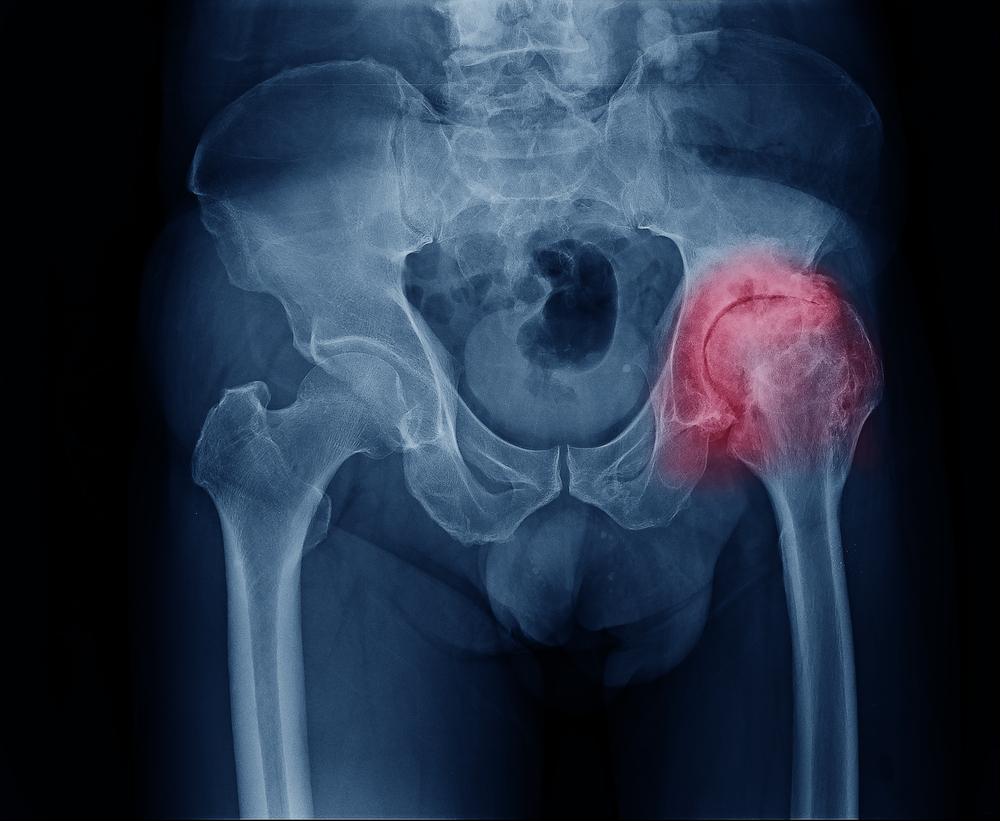

Коксартроз - заболевание тазобедренного сустава

Коксартроз — артроз тазобедренного сустава, заболевание опорно-двигательного аппарата. Это хроническое воспаление тазобедренного сустава, для которого характерно преждевременное разрушение хрящевой ткани, сужение суставной щели, уменьшение подвижности ноги со стороны поражения. Коксартроз часто диагностируется у людей с патологией костно-мышечной системы. В России эта болезнь является ведущей причиной нетрудоспособности у людей с болезнями суставов.

Диагностика коксартроза

Эффективное лечение тазобедренного сустава предусматривает первоочередное проведение подробнейшей дифференциальной диагностики. В первую очередь речь идет о рентгенографии, позволяющей определить состояние мягкой костной ткани в районе позвоночника.

Артроз - причина изменения сустава

Существует три степени тяжести артроза тазобедренного сустава:

Первая степень коксартроза. Для данной степени тяжести характерны умеренные болевые ощущения и отсутствие скованности при совершении движений. При проведении рентгенографического исследования можно заметить сужение суставной щели, а также возможны единичные костные наросты, остеофиты. Выявить коксартроз первой степени возможно только при прохождении рентгенологического исследования.

Вторая степень коксартроза. При второй степени тяжести наблюдается проявление ноющей боли. Стоит отметить, что в данном случае человек испытывает болезненные ощущения даже тогда, когда нога находится в состоянии покоя. При попытках развернуть стопу выпрямленной ноги влево и вправо боль усиливается. Человек с коксартрозом 2 степени хромает, иногда можно услышать хруст в суставе. При рентгенографии заметны деформация головки бедренной кости, а также многочисленные остеофиты и значительное сужение суставной щели (примерно на 1/3).

Третья степень коксартроза. Это наиболее тяжелая стадия заболевания, при которой человека постоянно беспокоят сильные болевые ощущения. При 3 степени коксартроза развивается мышечная атрофия (ягодиц и бедра) — у больного наблюдается «перекошенность» всего тела в сторону поражения. При рентгенологическом исследовании заметна глубокая деформация сустава и сужение суставной щели вплоть до полного соединения костных поверхностей.